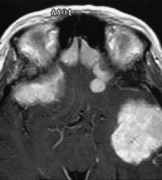

• 囊性脑膜瘤影像、病理特征和误诊原因的研究

囊性脑膜瘤影像、病理特征和误诊原因的研究

2022-01-05 17:23:12

囊性脑膜瘤临床少见,目前对它的了解较少,仅靠术前的影像学诊断是很困难的,临床常误诊为胶质瘤、转移瘤、血管母细胞瘤。治疗方案和预后评价存在...